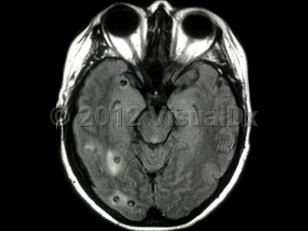

When food or water contaminated with T solium eggs is ingested by humans, the eggs hatch into embryos that egress into the blood stream through the intestinal mucosa. The embryos lodge in tissues of end organs and transform into larvae (cysticerci). Cysticercal cysts undergo 4 phases of development: the vesicular stage (cyst with a living larva), the colloidal stage (cyst with a degenerating / dying larva), the granular nodular stage, and the calcified stage. Of note, living larvae are only present in the first 2 stages (vesicular and colloidal), and these are the only stages that require and respond to antiparasitic therapy.

In neurocysticercosis, oncospheres (invasive larvae) enter the CNS. Depending on the location, neurocysticercosis is divided into parenchymal and extraparenchymal disease. The extraparenchymal form is further subdivided into ventricular, subarachnoid, Sylvian fissure, ocular, and spinal types. Patients with neurocysticercosis can be asymptomatic. When they are symptomatic, clinical presentations of parenchymal and extraparenchymal neurocysticercosis are distinctly different. Refer to the Look For section for further details.

Parenchymal neurocysticercosis is the most common cause of acquired epilepsy / seizure in endemic areas. Seizures can develop when the cysts are in viable or degenerative stages. Depending on the location and the number of the cerebral parenchymal lesions, patients can present with motor or sensory deficits, language difficulty, parkinsonism, or lacunar or large cerebral infarcts from cerebral ischemia or cysticercosis angiitis. When there is an intense inflammatory response around the cysts, patients become comatose, obtunded, or encephalopathic (cysticercosis encephalitis).